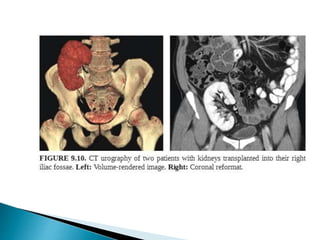

 Heterotopic renal transplantation.

1. Donor kidney is placed in an extra peritoneal location in

iliac fossa.

2. Renal artery and vein is anastomosed to external iliac

vessels

3. Urinary tract is reconstructed by an anti-refluxing

urterneocystostomy.